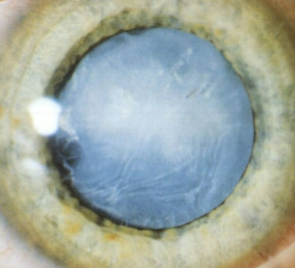

mature cataract

opaque cortex w/ intact capsule